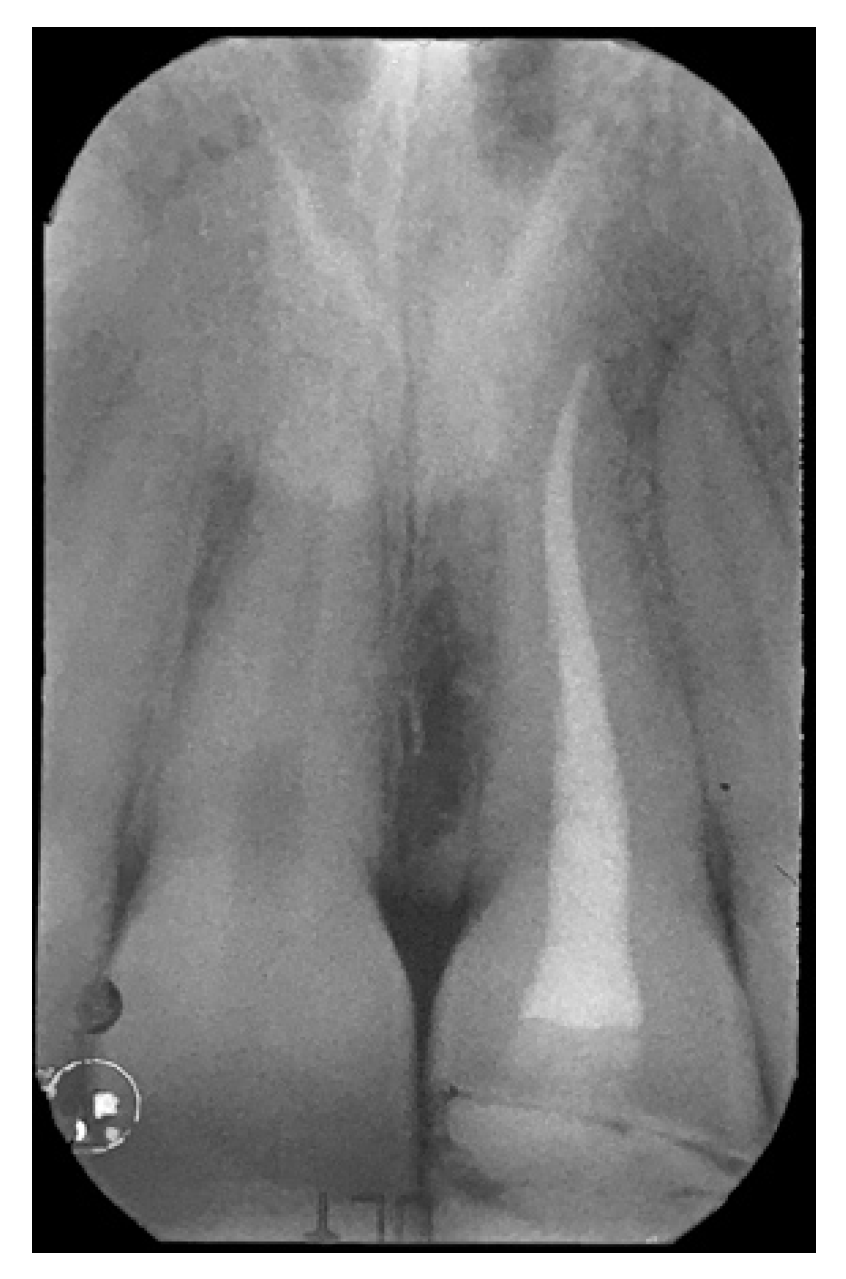

2. Case Presentation